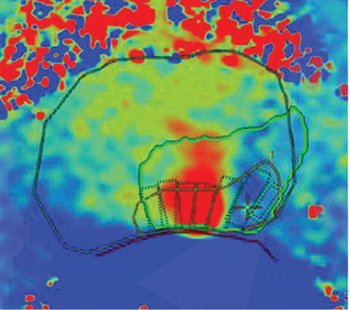

Men with intermediate-risk prostate cancer can be successfully treated with MRI-guided high-intensity focused ultrasound without experiencing incontinence or erectile dysfunction.

Pairing MR-guided high intensity focused ultrasound with the standard-of-care, external beam radiotherapy, can offer faster pain relief to patients.